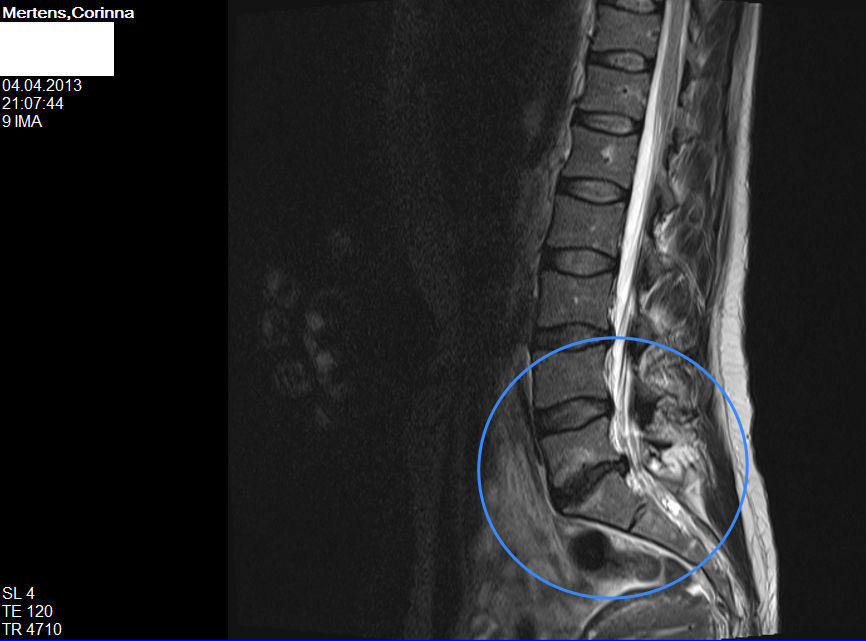

Diagnose Bandscheibenvorfall Und Osteochondrose L5 S1